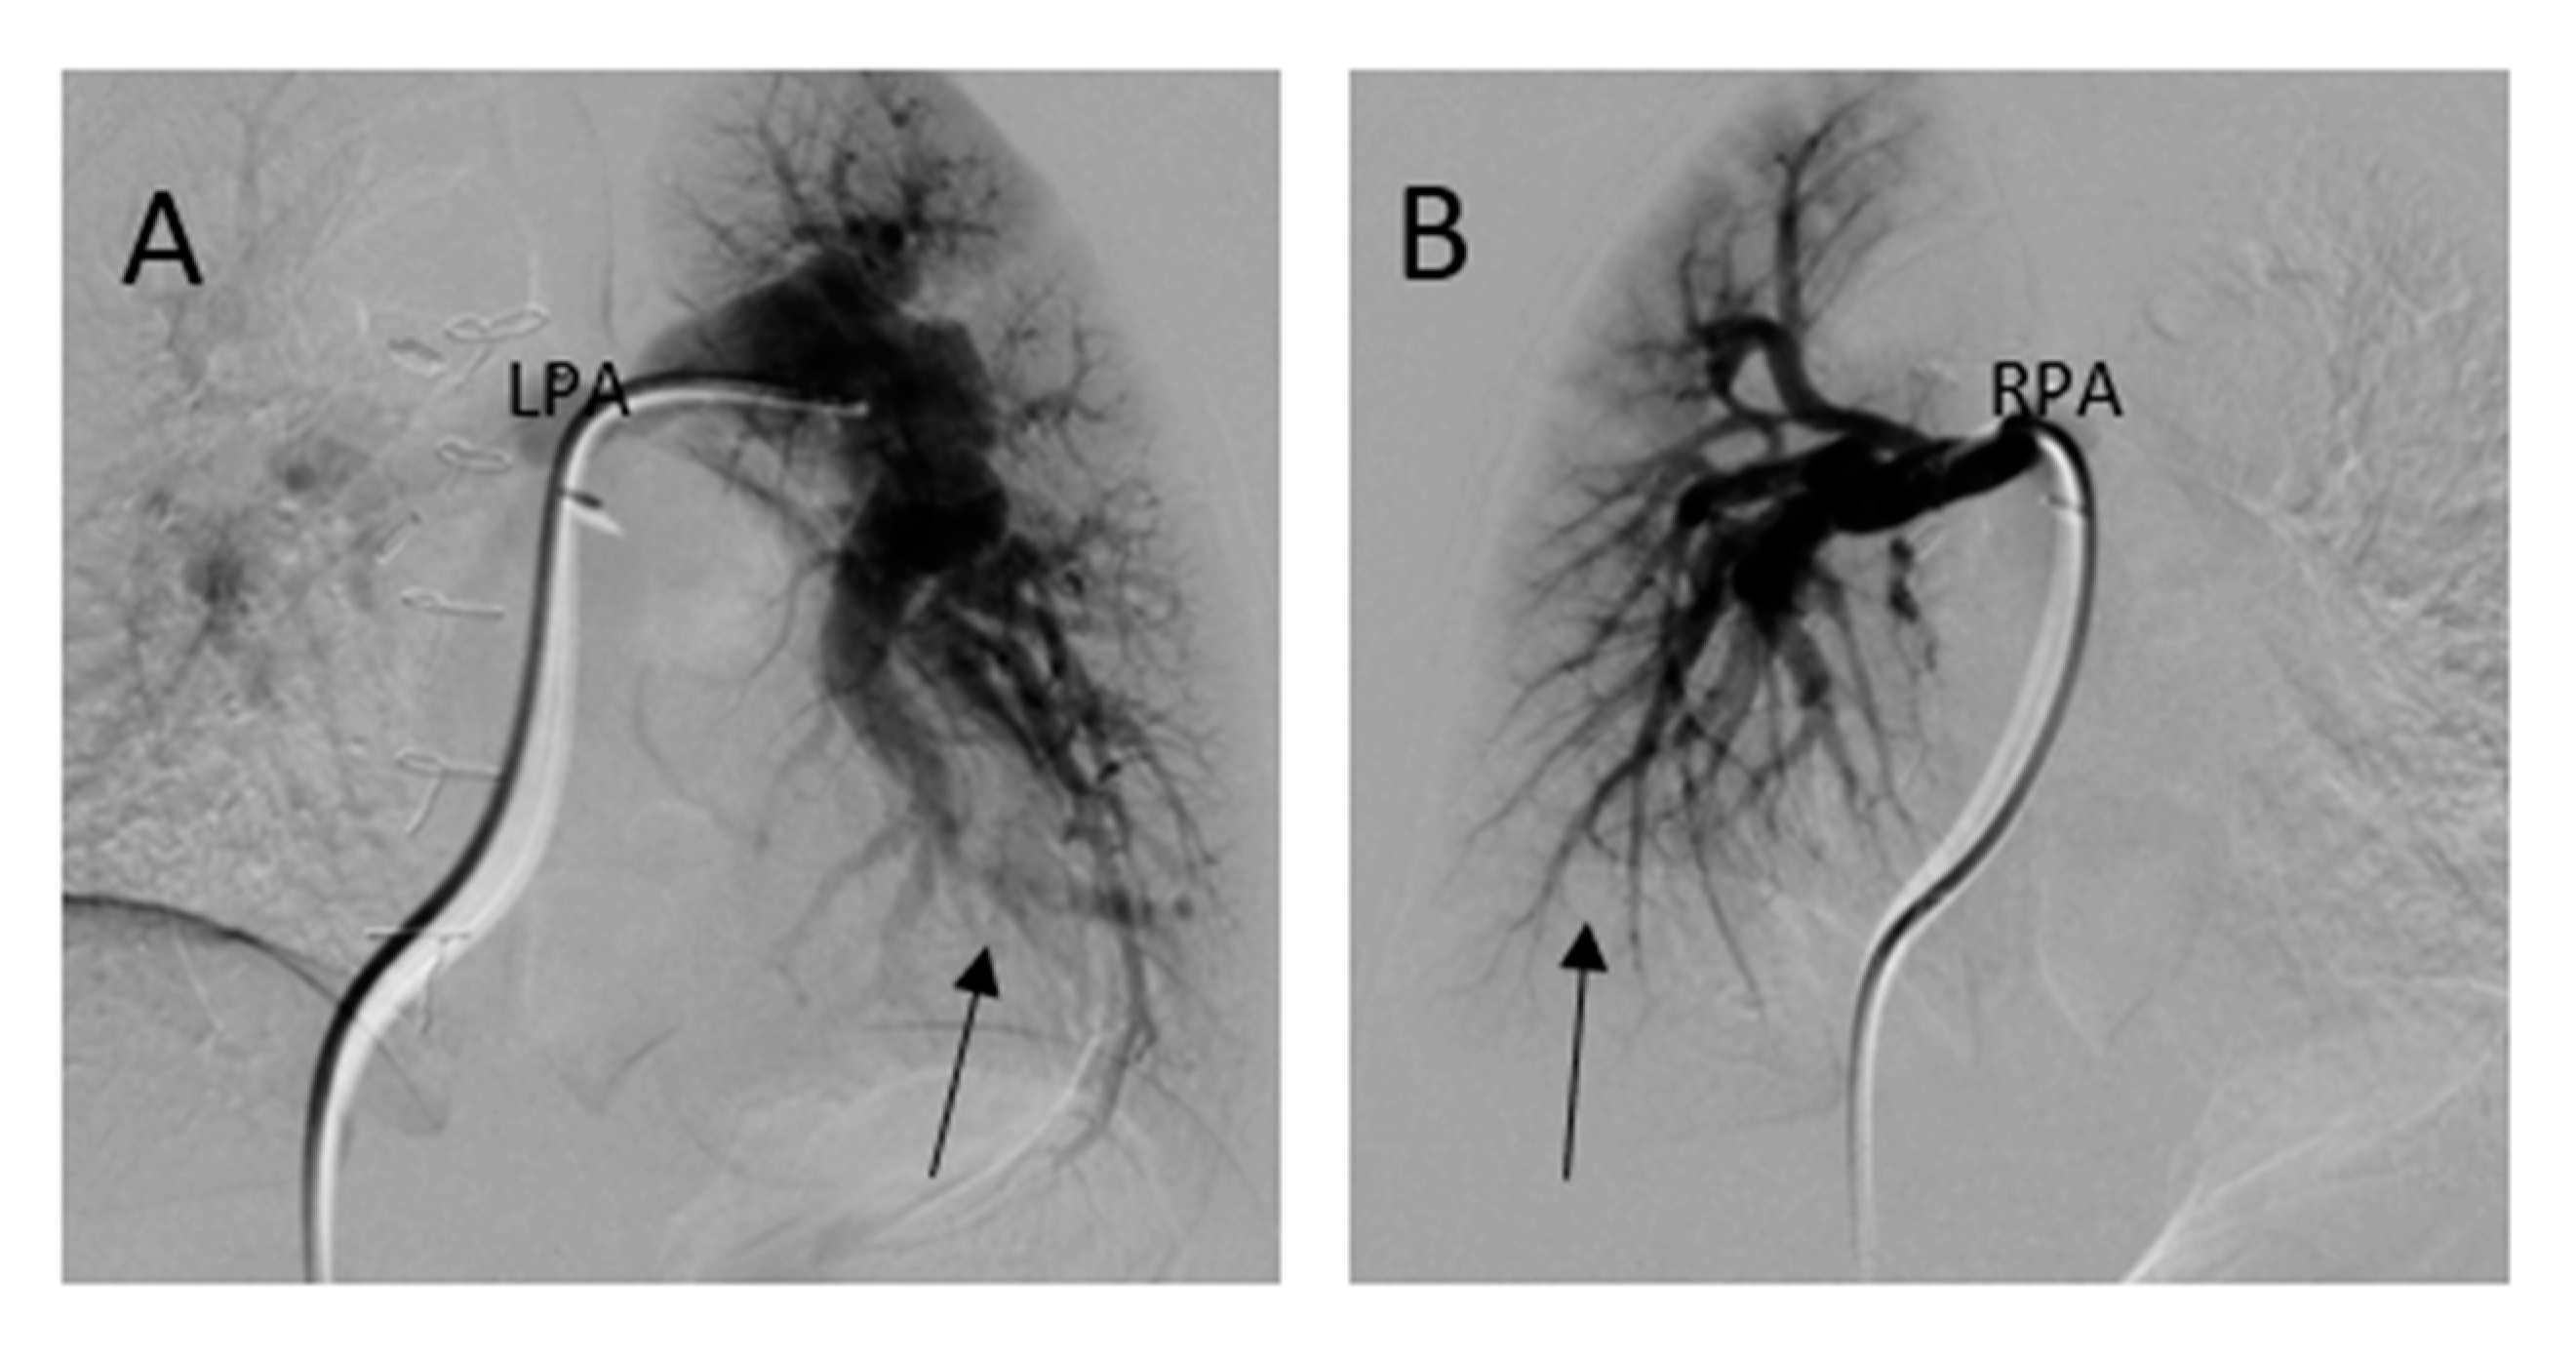

She underwent computed tomography (CT) angiogram of the chest which showed occluded right BT shunt and MAPCAs with a variable degree of stenosis supplying to bilateral lung fields (Figure 3). There were hypoplastic branch pulmonary arteries which were of ductal origin. She underwent cardiac catheterization and balloon angioplasty and stenting of MAPCAs. Her SpO2 increased from 60 to 75%. Selective angiogram of MAPCAs on the right side with digital subtraction showed the abnormal distal arborization of pulmonary vasculature suggesting vascular remodeling and PVD in the right upper lobe (Figure 4A) compared to the lower lobe (Figure 4B). She was discharged on aspirin, iron supplementation, and oxygen. On the latest follow-up 3 months after the interventional procedure, her functional capacity improved from NYHA class III to Class II.

Figure 4. Digital subtraction angiography of selective MAPACs. (A) MAPCA supplying the right upper lobe showed absence of normal arborization (arrow) and (B) the lower MAPCA showed relatively normal distal pulmonary vascular arborization pattern in right lower lobe (arrow).